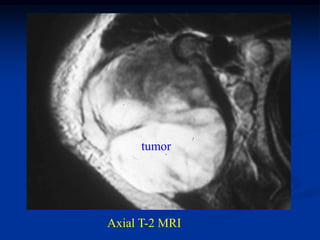

Case #1171

9 year male with desmoid tumor posterior axilla

tumor

CT scan

Axial T-2 MRI